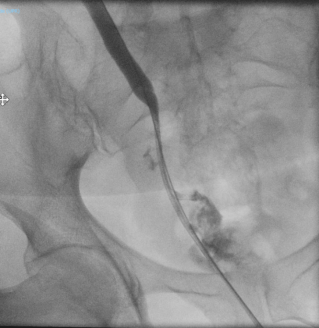

Case presentation

A 65-year-old woman with rectal adenocarcinoma (pT4bN0R2, KRAS-mutated) treated with neoadjuvant chemoradiotherapy, and extensive pelvic surgery developed chronic right-sided ureteral obstruction requiring long-term ureteral stenting. From 2023 onward, she experienced recurrent episodes of pyelonephritis, with urine cultures repeatedly isolating enteric organisms. In 2025, pelvic magnetic resonance imaging and retrograde ureteropyelography revealed right-sided hydronephrosis and a fistulous tract connecting the distal right ureter and the rectosigmoid colon, without evidence of tumor recurrence. Surgical management consisted of a bloc resection of the fistula, proctectomy with perineal closure, right ureteral reimplantation, terminal colostomy, and omentoplasty. The postoperative course was uneventful.